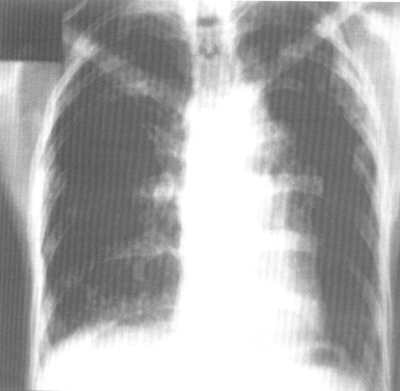

Альвеолит фиброзирующий идиопатический (синонимы: фиброз легочный идиопатический, синдром Хаммена-Рича) - прогрессирующее диффузное двухстороннее поражение альвеол и интерстициальной легочной ткани, сопровождающееся развитием диффузного фиброза и нарастающей дыхательной недостаточности. Фиброзирующий альвеолит имеет исключительно легочную локализацию, плохо поддается терапии, часто оканчивается летальным исходом. Фиброзирующий альвеолит - относительно редкое заболевание неясной этиологии, однако имеет тенденцию к возрастанию.